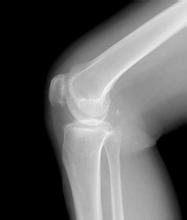

骨质增生常发现于颈腰椎和膝关节部位,因此,人们要避免长期剧烈运动。长期、过度、剧烈的运动或活动是诱发骨质增生的基本原因之一。尤其对于持重关节(如膝关节、髋关节),过度的运动使关节面受力加大,磨损加剧。长期剧烈运动还可使骨骼及周围软组织过度地受力及牵拉,造成局部软组织的损伤和骨髂上受力不均,从而导致骨质增生。 》》》骨质增生有哪些症状?云骨专家在线为你解答疑惑

人们在平时应减轻体重,这样可以减轻关节面的磨损,体重过重是诱发脊柱和关节骨质增生的重要原因之一。过重的体重会加速关节软骨的磨损,使关节软骨面上的压力不均匀,造成骨质增生。因此对于体重超标的人,适当的减轻体重可以预防脊柱和关节的骨质增生。>>>你会诊断你的骨质增生吗

膝关节骨质增生的治疗——德国关节镜技术

对于膝关节疼痛、积液等症状反复发作,膝关节存在变形、功能受限等症状的患者,经保守治疗无效的,可以考虑微创关节镜清理术。云南骨科医院引进全套进口德国西门子关节镜系统,定位有效、视野超清。